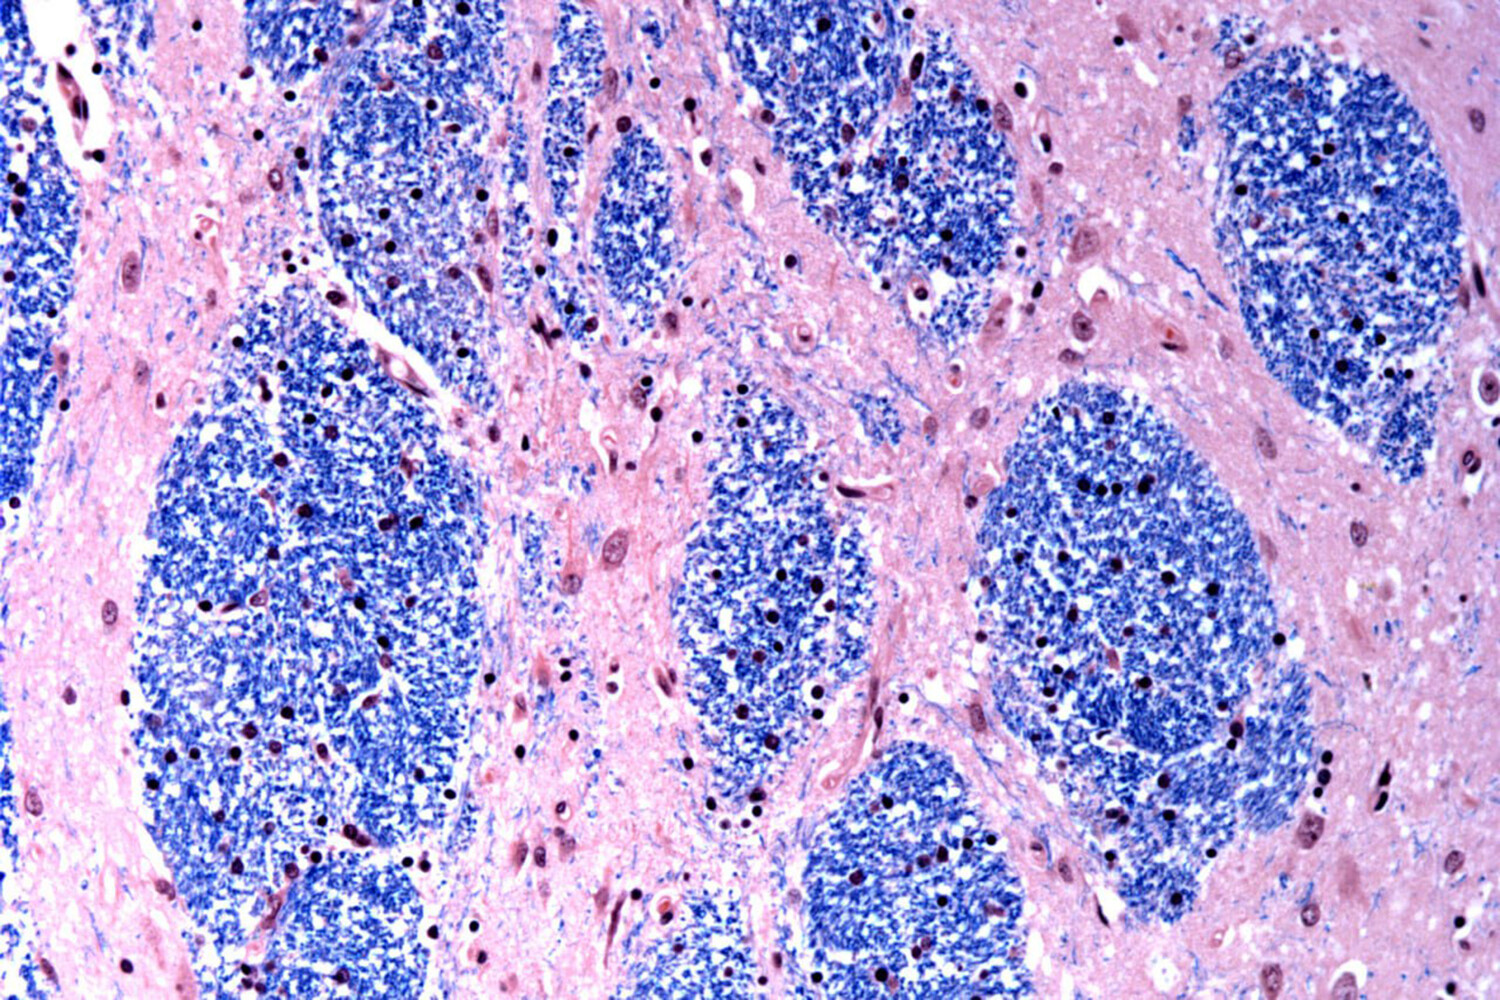

Наследственная природа заболевания проявляет себя преимущественно в возрастном диапазоне 30-50 лет. Патологический процесс затрагивает нейроны специфических зон мозга, что приводит к комплексным нарушениям двигательных функций, когнитивных способностей и поведенческих реакций. К сожалению, без своевременного вмешательства болезнь может иметь фатальные последствия.

Масштабное исследование охватило анализ образцов мозговой ткани от 103 доноров, включая 53 пациента с подтвержденным диагнозом и 50 здоровых добровольцев, что обеспечило высокую достоверность полученных результатов.